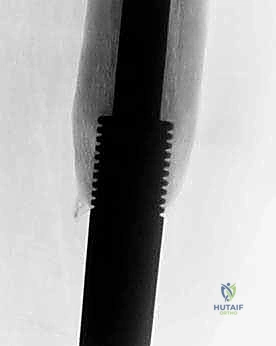

The Minimally Invasive Expandable Prosthesis (e.g., the JTS implant) is lengthened via an internal worm-drive mechanism. It requires a minor percutaneous procedure where an Allen key is inserted through a small stab incision to manually turn the mechanism. While highly reliable and mechanically robust, it carries a cumulative risk of infection with each lengthening procedure. Conversely, Non-invasive Expandable Prostheses (e.g., Repiphysis or Mutars Xpand) utilize an internal electromagnetic motor driven by an external magnetic coil placed over the limb in the outpatient clinic. This eliminates the need for repeated anesthesia and surgical incisions, drastically reducing the risk of secondary periprosthetic joint infection, though these devices are mechanically more complex and historically prone to internal mechanism failures.

Canal Preparation and Implant Trialing

Following resection, the remaining host bone canal must be prepared. In pediatric patients, the intramedullary canal is often narrow, necessitating careful sequential reaming. We must balance the need for adequate implant stem diameter (for mechanical strength) against the risk of iatrogenic cortical perforation or fracture.

If cementing, a cement restrictor is placed, the canal is pulsatile-lavaged and dried, and third-generation cementing techniques (vacuum mixing, retrograde injection) are employed. The definitive prosthesis is impacted into place, ensuring correct version.